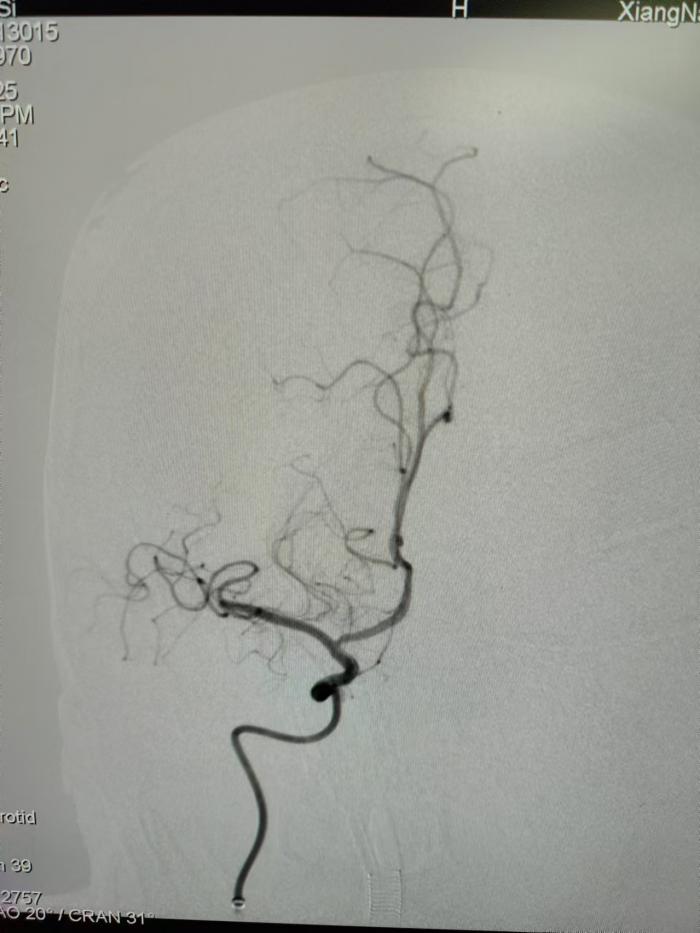

取栓后,血栓取出,血管血流恢复,不影响脑部功能,从而避免卒中后致残的发生。